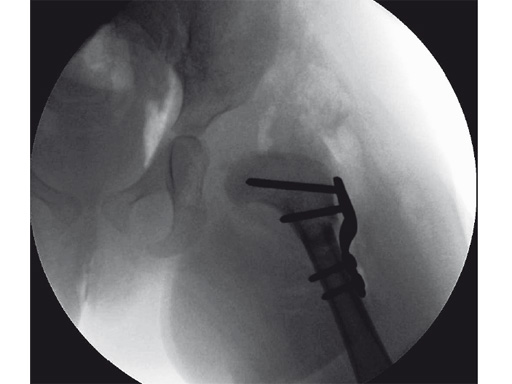

An 18-month old girl presented with developmental dysplasia of the hip. She had failed conservative management with a Pavlik harness, and redislocated following open reduction and femoral osteotomy of the right hip. She underwent revision open reduction and femoral osteotomy of the right hip, followed by the same procedure on the left hip 6 weeks later.

Case provided by James B Hunter, Nottingham, UK